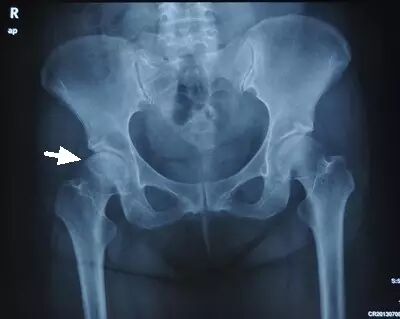

II期病人有髋部症状,磁共振出现异常,X线片显示股骨头出现透光和硬化改变

III期磁共振出现异常,X线片显示软骨下塌陷(新月征),股骨头内出现空洞,股骨头没有变扁